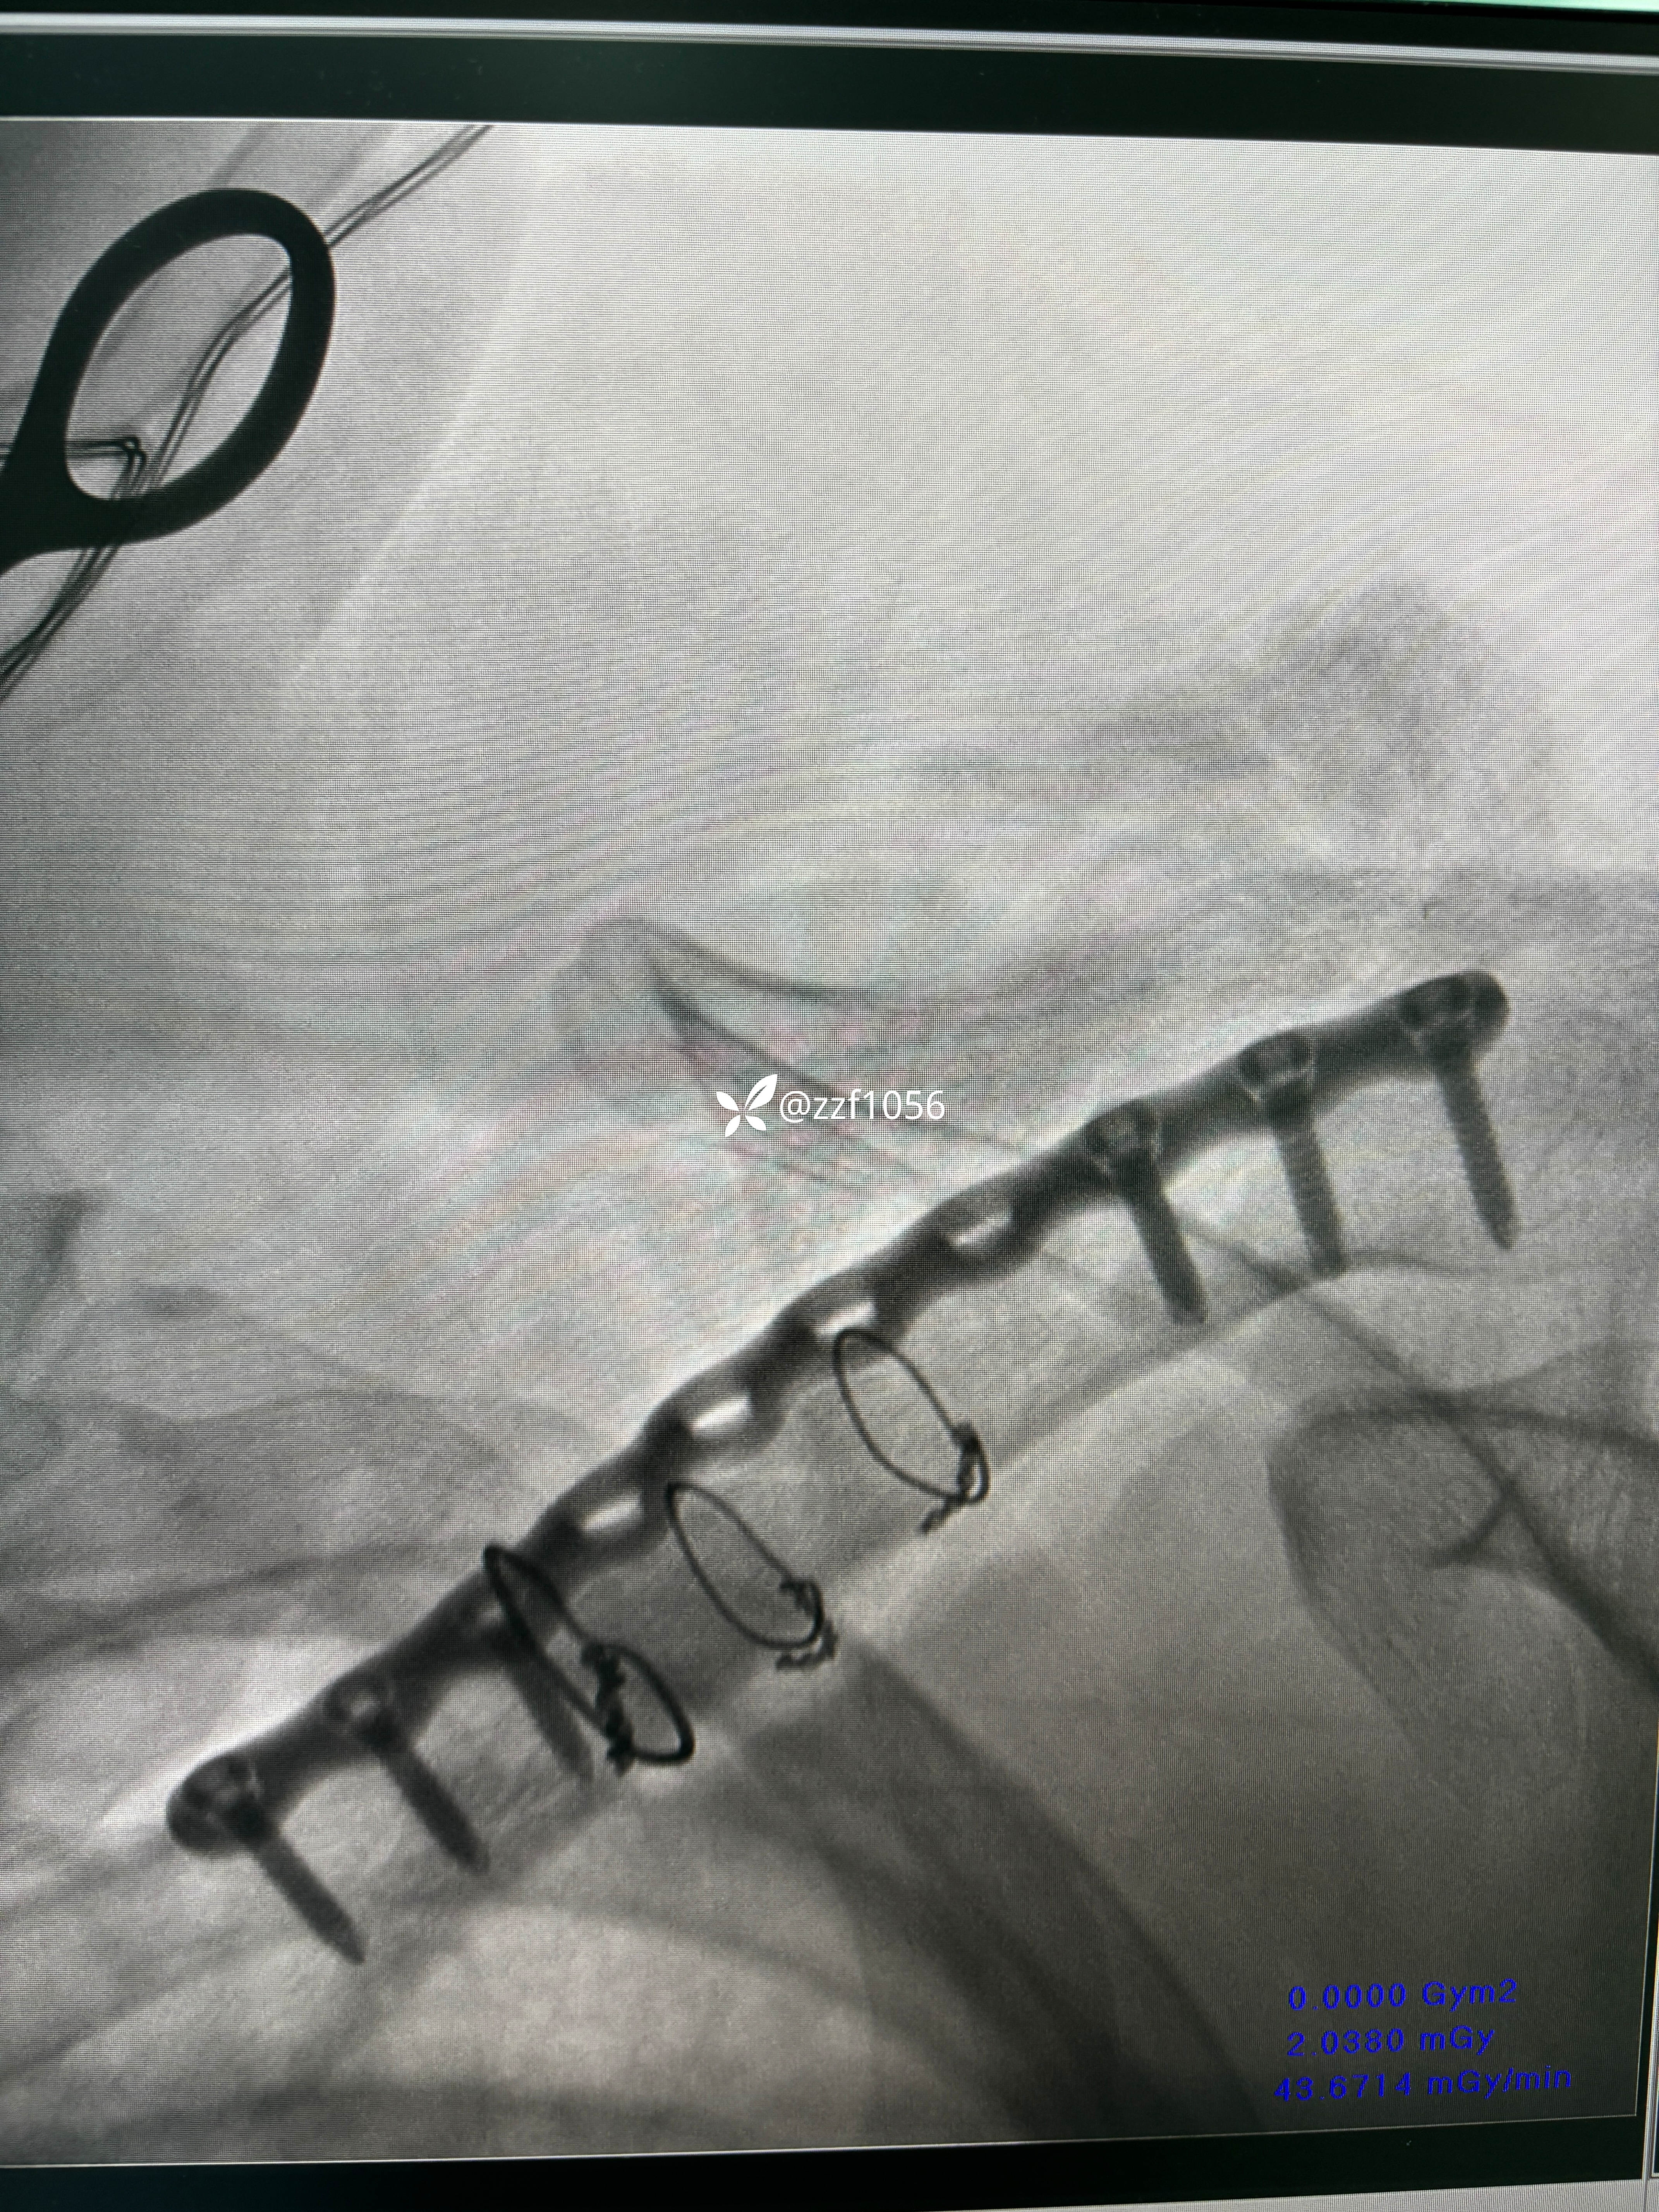

术中作切口后探查未见皮神经,保护好骨膜,清理折端复位临时克氏针固定,后方蝶形骨块较大,nice结改2道钢丝捆扎,复位良好,取最长10孔钢板,貌似钢板有点短,远折端3枚锁定螺钉有效固定,近折端只有2枚螺钉有效固定,第3枚螺钉失效且后方仍有骨块微翘,无奈增加一枚钢丝适宜捆扎。

2.骨折端跨度较大,接骨板偏短,会出问题吗?器械厂家告知这是最长锁骨钢板,貌似用过12孔,现在单用钢板器械商都不愿意发了。